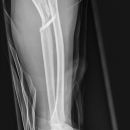

Unterarmschaft Fraktur